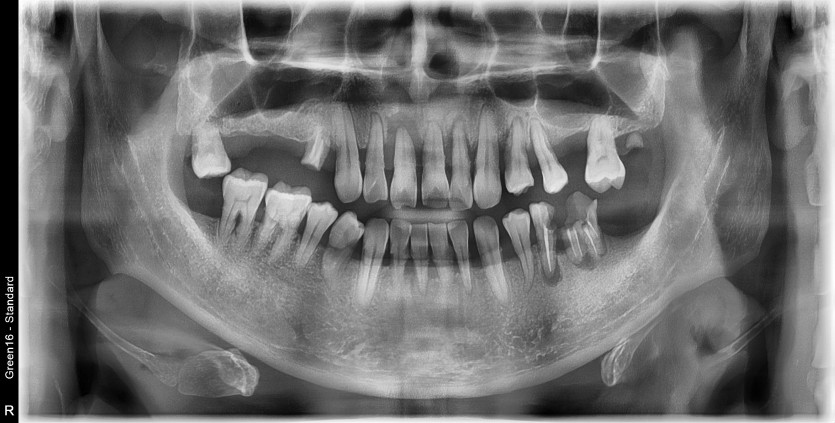

전체 임플란트 증례입니다.

18개의 임플란트로 완성하였습니다.